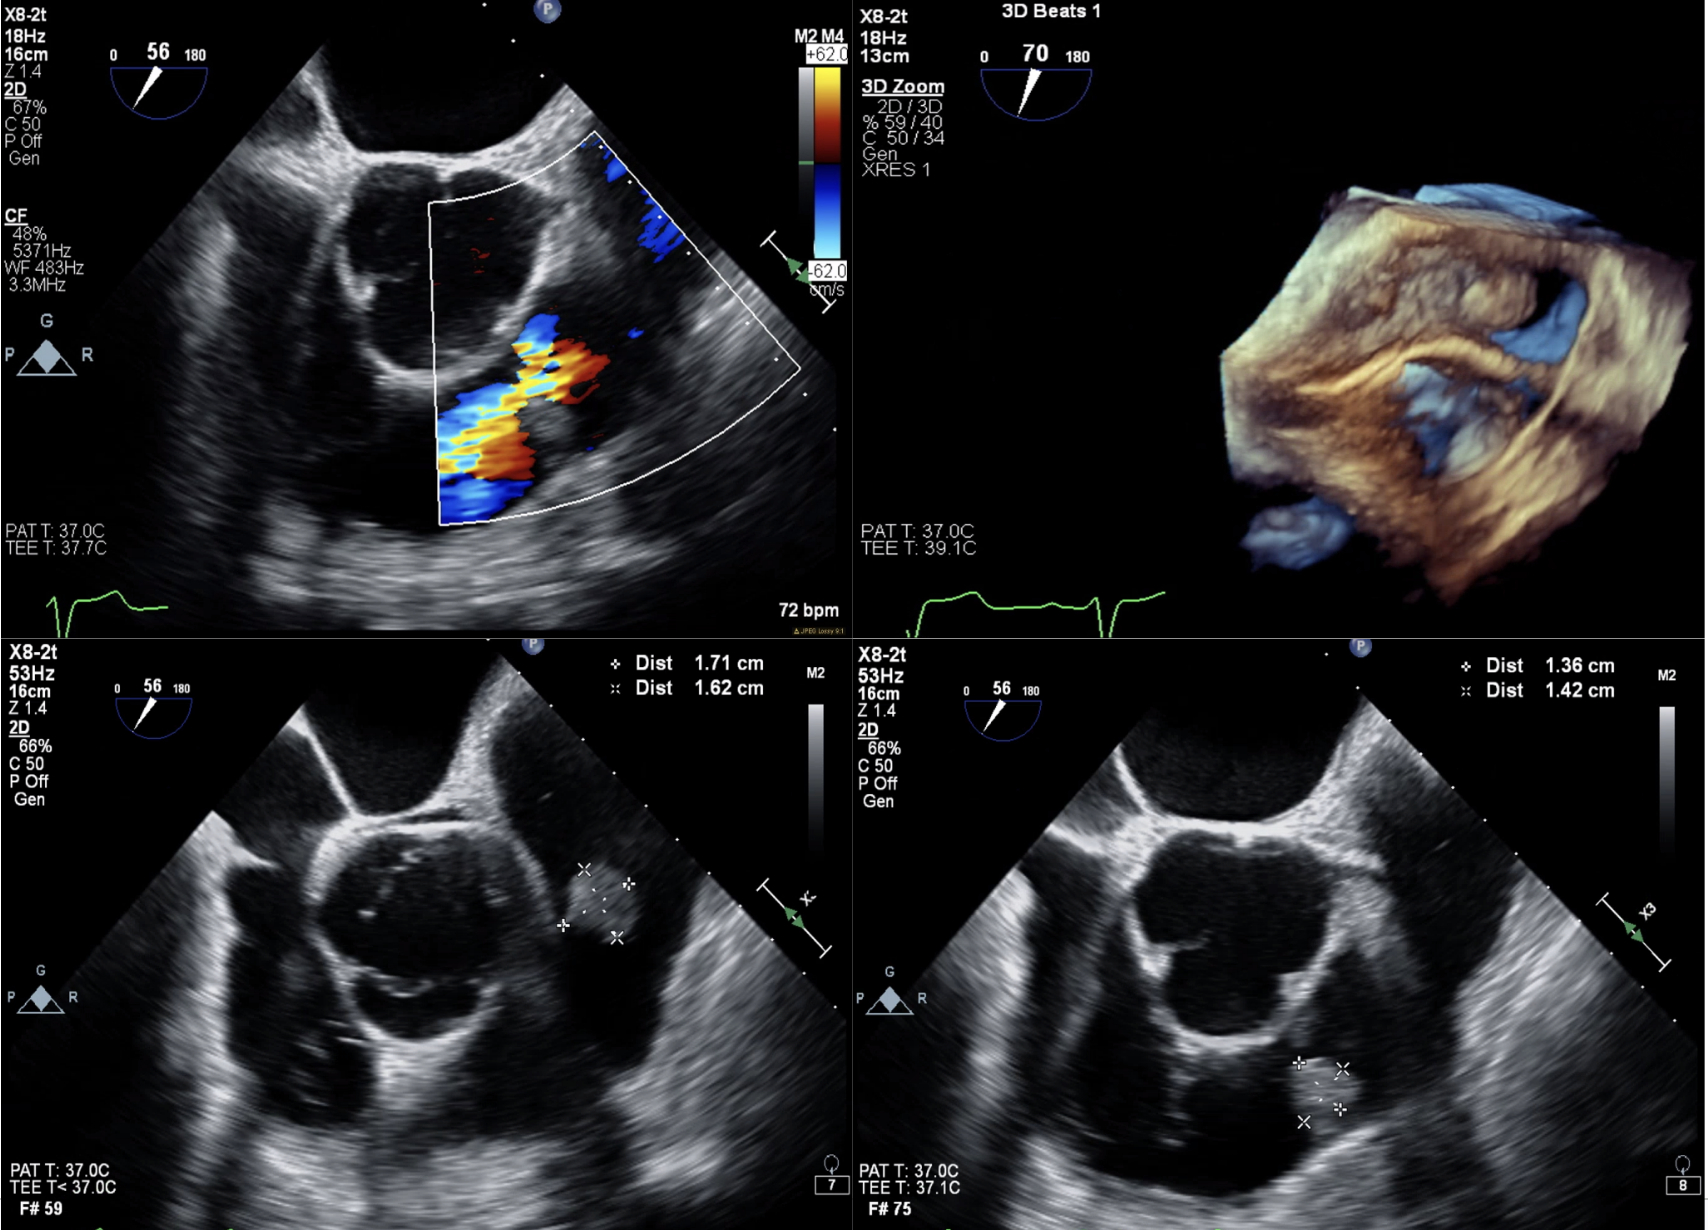

A 63-year-old male with diabetes, coronary artery disease, and recent ureteral stenting for nephrolithiasis (complicated by E. faecalis urinary tract infection) presented with malaise, chills, and polyuria. Initial evaluation revealed diabetic ketoacidosis, acute kidney injury, and E. faecalis bacteremia. Despite IV antibiotics, blood cultures remained positive for 10 days. Transesophageal echocardiogram (TEE) showed a pulmonary valve mass and moderate-to-severe regurgitation. Due to persistent infection, he underwent coronary artery bypass grafting and pulmonary valvectomy, revealing vegetations and a perforated cusp. Pathology confirmed E. faecalis endocarditis, ruling out tumors. Valve replacement was deferred due to recent bacteremia. Postoperatively, multifactorial shock required extracorporeal membrane oxygenation and mediastinal washouts for hemorrhage. Five days later, a 29-mm bioprosthetic pulmonary valve was implanted. The patient recovered and was discharged to rehabilitation.

This case highlights the challenge of diagnosing isolated pulmonary valve IE, especially with E. faecalis, given its rarity. The 2023 Modified Duke/ISCVID criteria, supported by TEE findings, confirmed IE. Persistent bacteremia necessitated surgery, consistent with complicated IE guidelines. The absence of risk factors and spheroid mass appearance initially suggested a tumor, but pathology clarified endocarditis. Right-sided IE is rare due to low pulmonary valve shear stress, making this case notable. Postoperative shock from blood loss and vasoplegia underscored the need for intensive management. Delayed valve replacement reduced reinfection risk, yielding a good outcome for this patient.

Isolated pulmonary valve IE due to E. faecalis is rare and requires high degree of suspicion for diagnosis in persistent bacteremia. TEE, surgery, and delayed valve replacement were critical, demonstrating tailored management for favorable outcomes in complex IE.